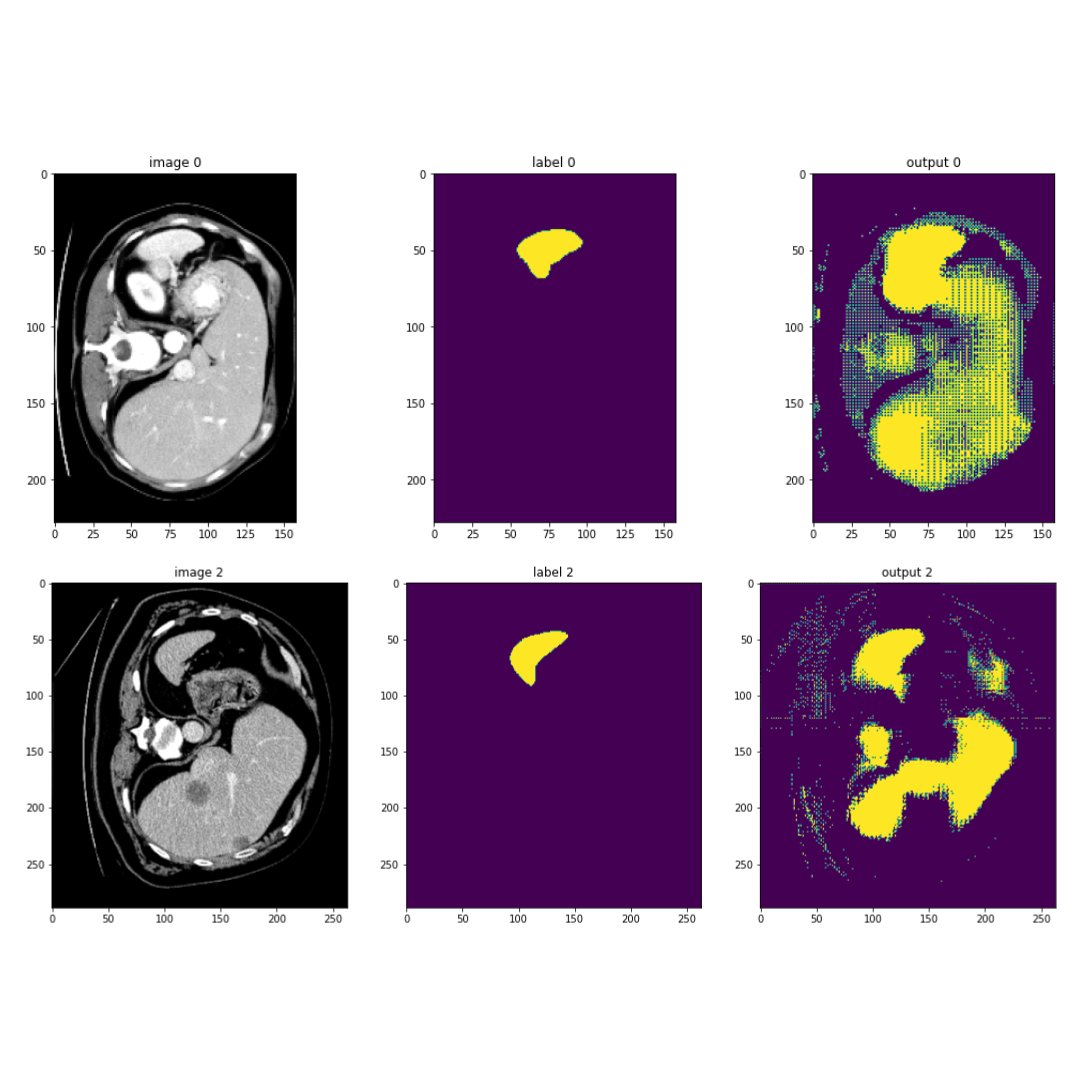

Spleen, Liver, and Pancreas Segmentation using MSD Challenge Dataset

This project focuses on medical image processing tasks, specifically organ segmentation of the spleen, liver, and pancreas using the Medical Segmentation Decathlon (MSD) challenge dataset. It is primarily utilizing UNET-based models for segmentation tasks, but looking into UNETR aswell. The project allows for various augmentations and model selections, including UNET and UNETR for 3D image segmentation with transformers. The code is utilizing fastMONAI.